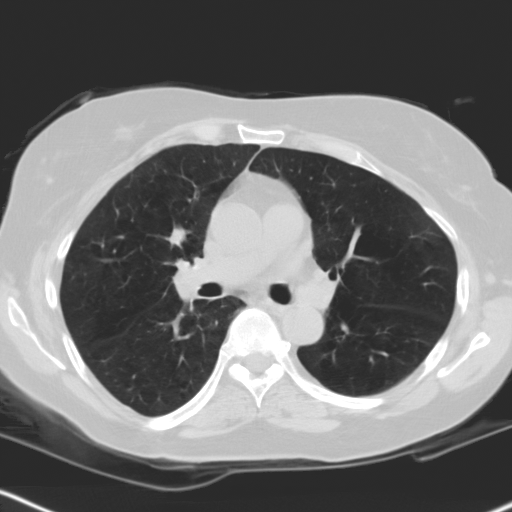

Choose if image shown above is Real or Fake :

Real

Fake